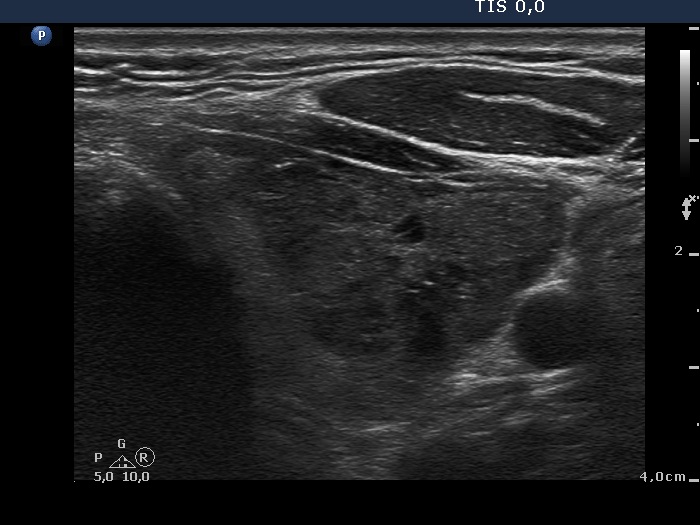

Three years after the first examination (ultrasonographic picture 6)

Left lobe, another transverse scan.